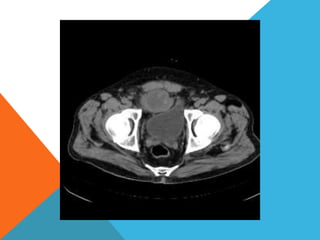

El paciente presentó síntomas de sangrado digestivo y pérdida de peso. Exámenes revelaron gastritis crónica asociada a H. pylori. Un tumor fue descubierto en una colonoscopia normal. La cirugía removió un tumor fibroide solitario, una rara neoplasia mesenquimal que usualmente crece lento y tiene bajo potencial de malignidad. El pronóstico después de la remoción quirúrgica es generalmente bueno.